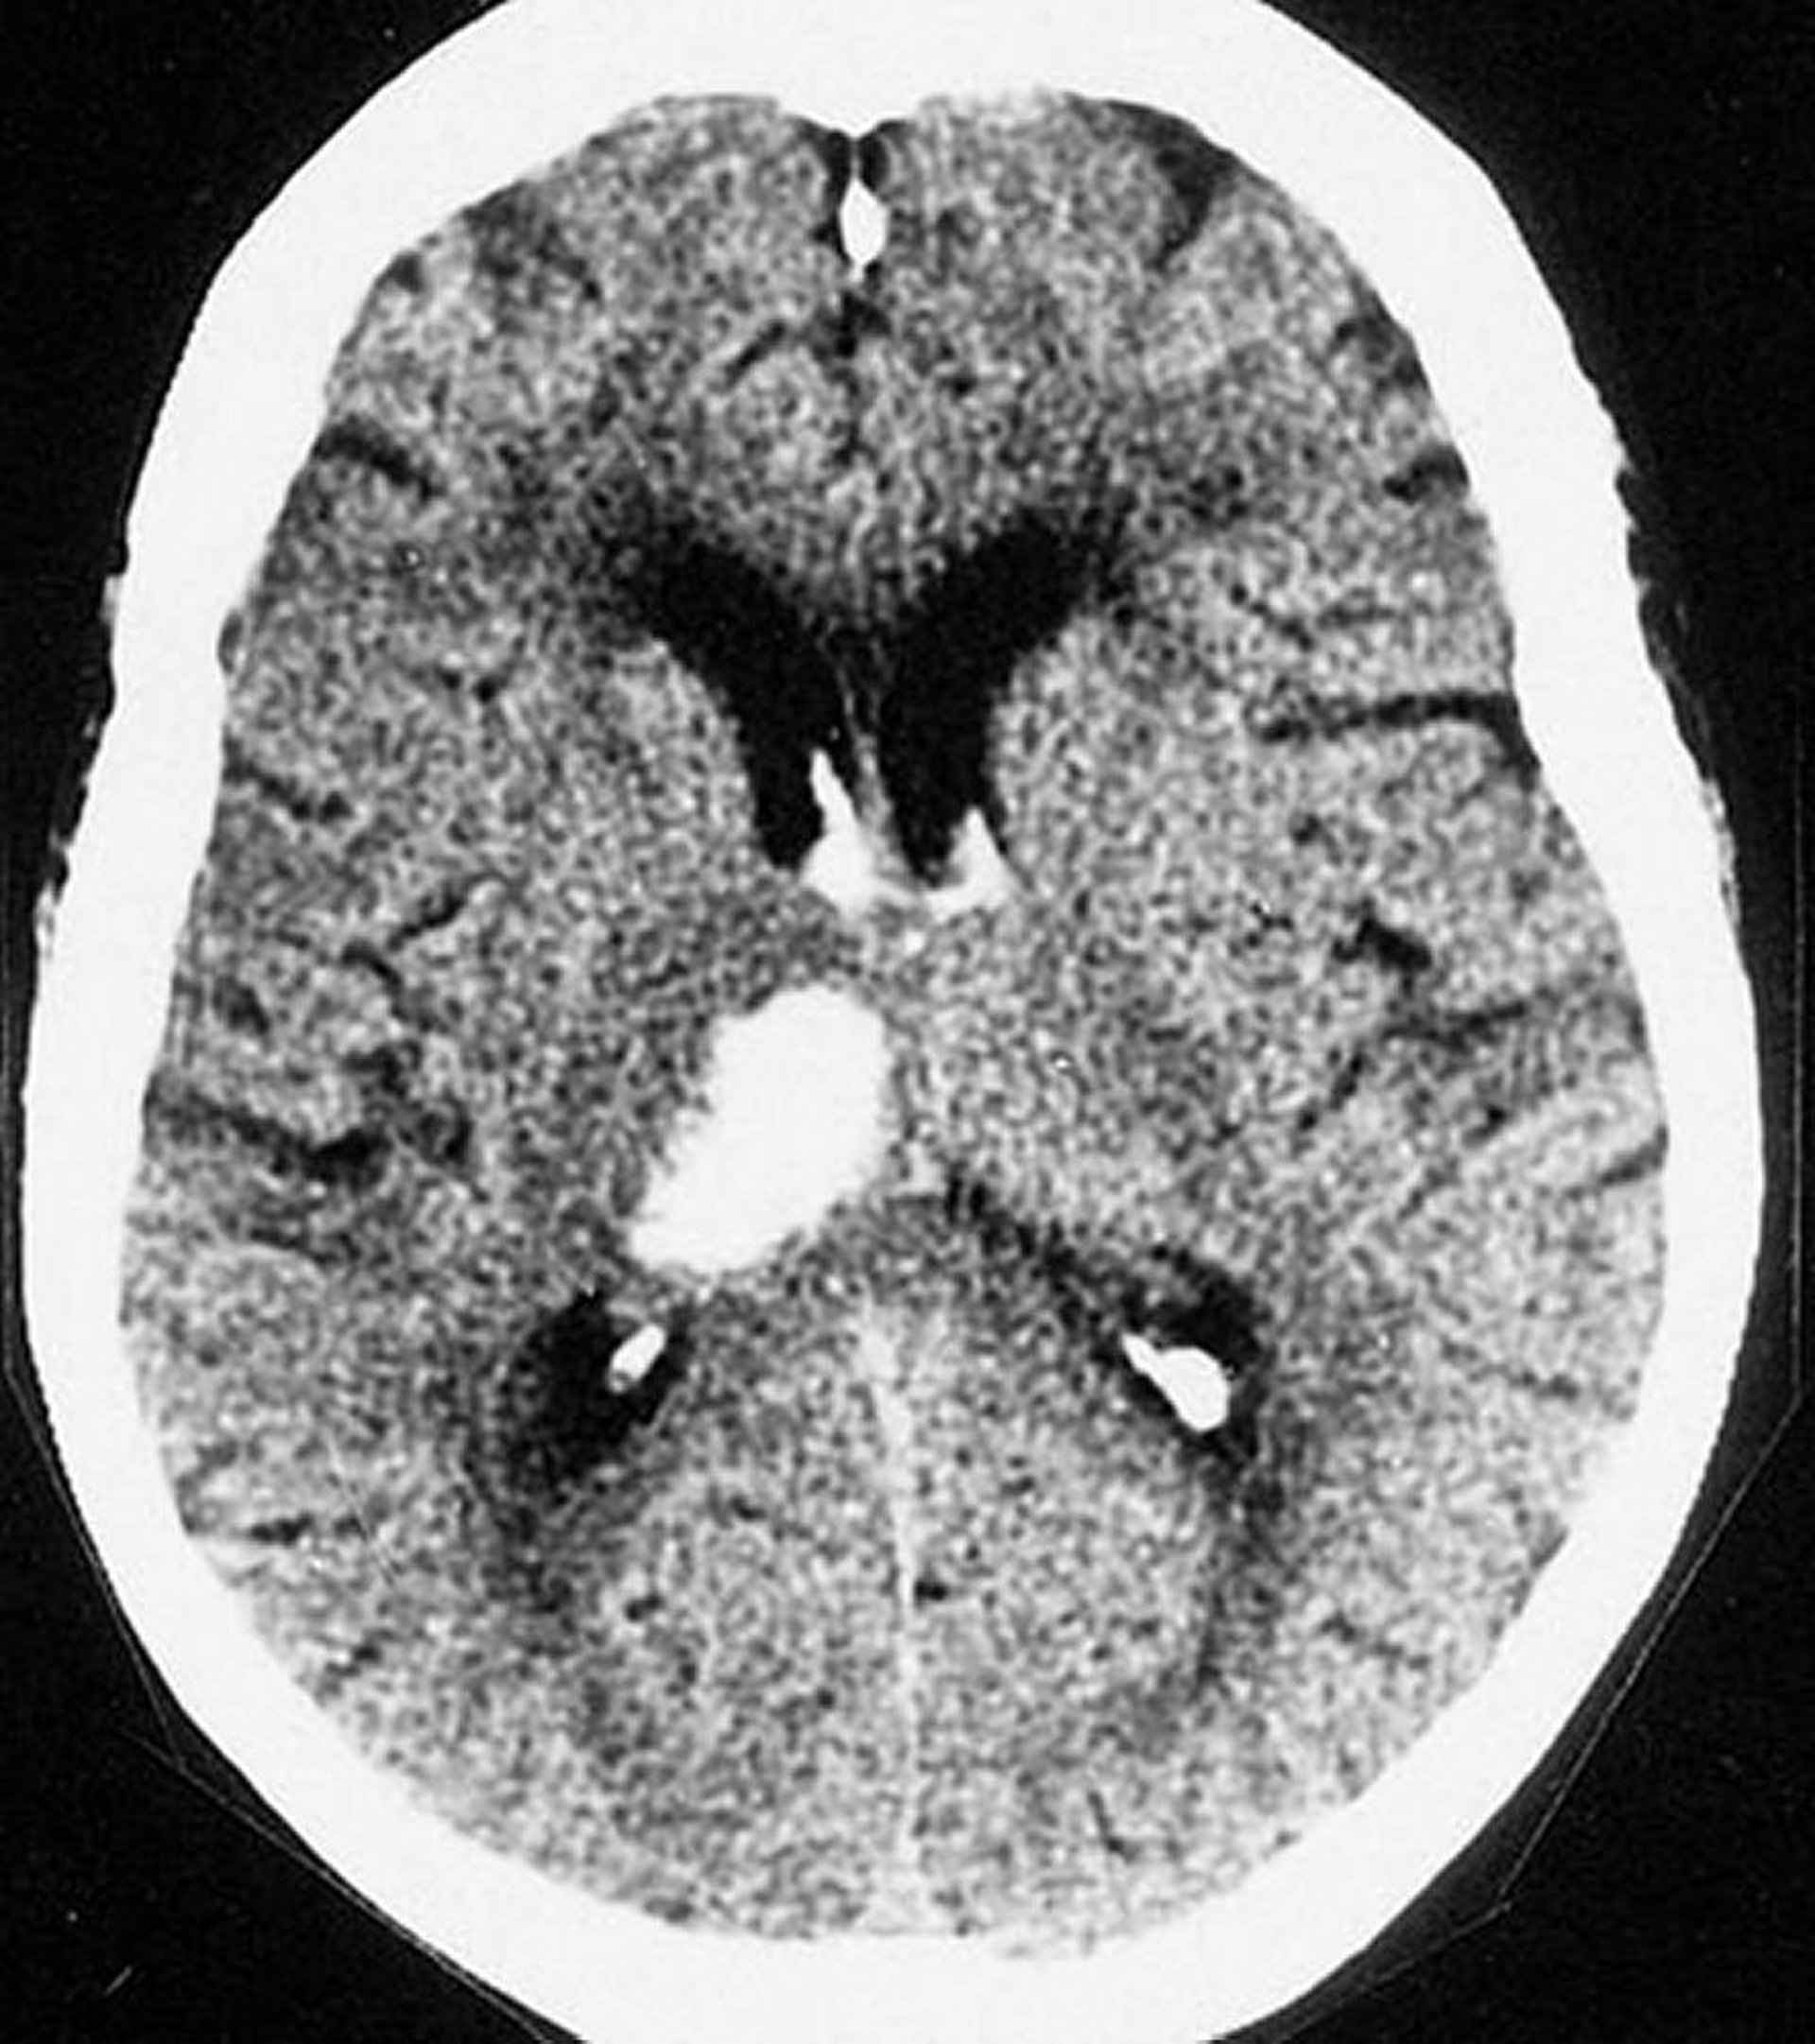

脳内出血(視床)

このCT画像では,視床に出血を認める。脳内出血は視床および基底核内に生じることが多い。

By permission of the publisher.From Furie K, et al.In Atlas of Clinical Neurology.Edited by RN Rosenberg.Philadelphia, Current Medicine, 2002.